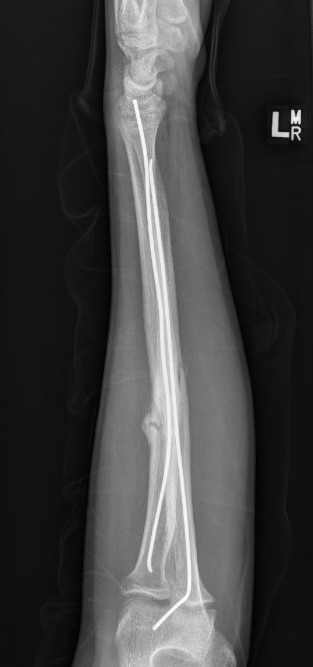

3. Intramedullary elastic nail

TENS technique

Technique

Radius (typically first as more difficult to reduce)

Entry point with awl 2 cm proximal to distal physis

1. Radial styloid / distal lateral entry

- ensure radial nerve / cephalic vein, 1st extensor compartment protected

2. Listers tubercle / dorsal entry

Elastic Nail size

60 - 70% of the intramedullary canal

Typically 1.5 - 2.5 mm

Cut nail

Withdraw 1 cm, cut with endcutter, then advance

Ulna (usually reduced after radius fixation)

Entry point 2 cm distal to apophyseal plate

1. Proximal lateral

- avoids ulna nerve

3. Distal medial

Postoperative

Cast in supination to tighten interosseous membrane

Cast 6 weeks

Removal of TENS at 4 - 6 months once osseous union established